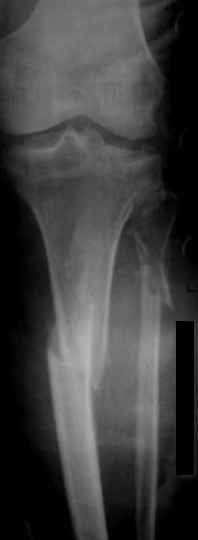

Уважаемые коллеги, случай интересен прежде всего тем, что в данном переломе присутствуют два компонента - внутрисуставной и метадиафизарный, требующих соблюдения разных принципов при хирургическом лечении. Для внутрисуставного компонента необходима анатомичная репозиция с межфрагментарной компрессией и достижением абсолютной стабильности. При наличии импрессии надо быть готовым к замещению дефекта. Артротомию выполнять придётся, но она может быть достаточно деликатной, что, впрочем, не всегда возможно. И здесь хорошим подспорьем является предварительно наложенный аппарат внешней фиксации. Для артроскопически ассоциированной репозиции всё-таки лучше подходят случаи с преобладанием импрессии, а не раскалывания, как у данного пациента.

Для метадиафизарной части этого повреждения обнажение перелома с анатомичной репозицией не является абсолютно необходимым, и, более того, неизбежно приведёт к деваскуляризации кости и возможным проблемам с заживлением перелома. Для этой части перелома желательно шинирование без обнажения зоны перелома. Шинирование может быть интрамедуллярным соответствующим гвоздём или экстрамедуллярным (пластиной или аппаратом внешней фиксации). Главное для метадиафизарной части перелома - это восстановление длины, оси конечности с правильной ротационной установкой и достижением относительной стабильности.

В заключение - клинический пример хирургического лечения похожего перелома из моего архива (1,2). После анатомичной репозиции суставной поверхности с введением стягивающего винта замещён дефект (3,4). Метадиафизарная часть перелома шинирована блокированной пластиной без обнажения отломков (5,6,7).